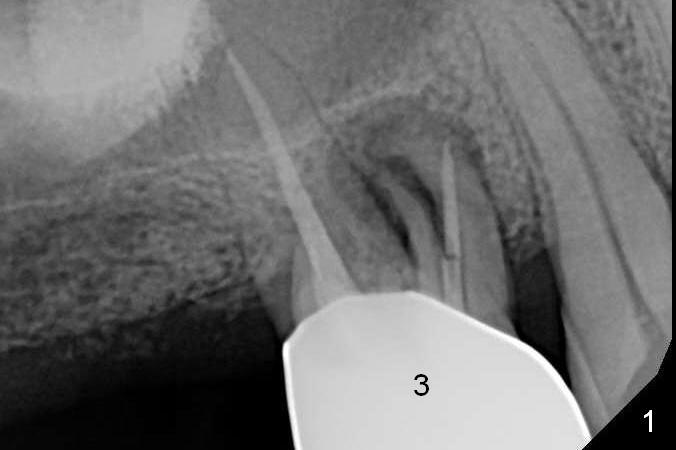

A 56-year-old man has discomfort associated with the tooth #3 one year and a half after root canal therapy (Fig.1: mesiobuccal root vertical fracture). Since an implant is just placed at #19 and another one will be encouraged to be placed at #2 (Fig.2), root amputation may be a valid treatment modality (Fig.3,4). After debridement and Clindamycin topical application, allograft/Osteogen is placed (Fig.5,6 (dashed line)), followed by Osteogen plug (Fig.7 *). Discomfort apparently shifts to the distobuccal root 9 months postop, while the MB defect seems to heal (Fig.8 *). Extraction and implant is expected.